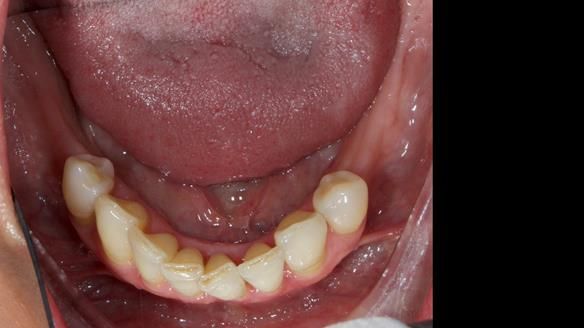

This is one of those cases that reminds me why I love removable prosthodontics. Pam was an absolute joy to treat — we were on the same page throughout. Her old upper flexible denture was loose, uncomfortable, and unaesthetic. We replaced it with a carefully designed metal-based upper partial denture/splint and new porcelain-bonded-to-zirconia (PBZ) crowns for the canines. The result is stable, comfortable, and natural-looking.

- Diagnosis and plan – Flexible upper denture ill-fitting with poor stability, retention, and appearance. Plan: metal-based upper partial denture/splint with lighter porcelain-bonded-to-zirconia crowns on UR3 and UL3.